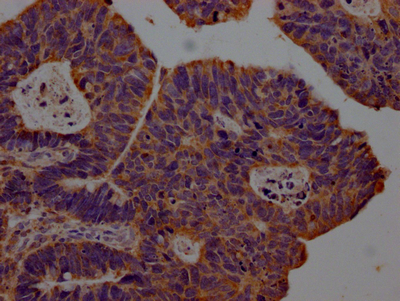

IHC image of CSB-RA903061A0HU diluted at 1:100 and staining in paraffin-embedded human ovarian cancer performed on a Leica BondTM system. After dewaxing and hydration, antigen retrieval was mediated by high pressure in a citrate buffer (pH 6.0). Section was blocked with 10% normal goat serum 30min at RT. Then primary antibody (1% BSA) was incubated at 4℃ overnight. The primary is detected by a Goat anti-rabbit IgG polymer labeled by HRP and visualized using 0.05% DAB.